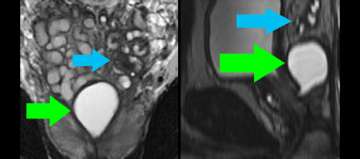

8) Benign Disease (Infertility)

Benign Disease (Infertility)

• Young man presents with infertility (azospermia)

• Workup and medical history otherwise noncontributory

• Muellerian duct remnant in central upper prostate may obstruct ejaculatory ducts

• Left seminal vesicles are atrophic